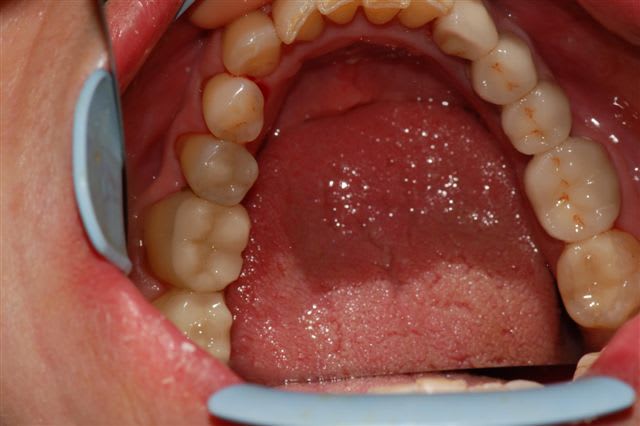

voici un cas traité en dentisterie globale à l'aide du laser en paro et du cerec en occluso, le cas à été terminé en 2010, cette semaine examen microbiologique de routine avec maintenance paro, il n'y a plus de flore pathologique dans la bouche de cette patiente

emma écrivait:

> voici un cas traité en dentisterie globale à l'aide du laser en paro et du cerec

> en occluso, le cas à été terminé en 2010, cette semaine examen microbiologique

> de routine avec maintenance paro, il n'y a plus de flore pathologique dans la

> bouche de cette patiente

>

> Emma

Reste plus qu'à faire des greffes de gencives secteur 4.

salut ceramik, toujours aussi contente de te lire, tes désirs sont des ordres, radios faites en 2010, les photos dates de juin 2010, les papilles entre 11 et 21 sont entrain de se reconstruire petit à petit, au prochain contrôle de maintenance, je ferai des radios et des photos pour montrer l'évolution engendrée par la biostimulation laser diode.

Joli cas Emma, juste une remarque, le travail de l'espace inter incisif en jouant sur la convexité des profils d'émergence masquerait le manque immédiat de papille et à terme la papille se reconstruirait plus rapidement.

Il est vrai qu'au vu de la difficulté initiale du cas ce type de détail peut passer à la trappe.

très belle reconstruction par cfao directe!!!!!

merci vm, en effet, le cas était plutôt complexe, comme la plupart des cas en dentisterie globale, mais ce que je voulais souligner, c'est que le Cerec pour ne pas le nommer permet de rendre de grands services.